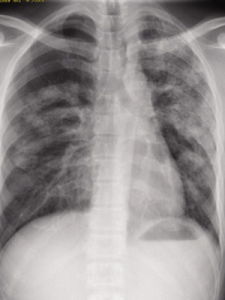

肺部小結節是胸外科常見又較難確診的疾病,生理解剖發現呈多發性,可互相融合成塊狀,也有單發性,肺部圓形結節,直徑1-2cm,後期可發生空洞,或合併感染。

肺部小結節肺部小結節是胸外科常見又較難確診的疾病,它的診治一直是臨床上的難點、討論的熱點,其病因複雜,臨床表現缺乏特異性,診斷有一定的難度,易誤診和漏診。周圍型肺癌瘤體直徑≤2cm者稱為小肺癌,直徑≤1cm者稱為微小肺癌。小肺癌並不完全是早期肺癌,特別是腺癌、小細胞未分化癌,文獻報導有20%左右的小肺癌患者有淋巴結的微小轉移。因此一些患者錯過最佳手術時機。

肺部小結節生理解剖發現呈多發性,可互相融合成塊狀,也有單發性,肺部圓形結節,直徑1-2cm,後期可發生空洞,或合併感染。